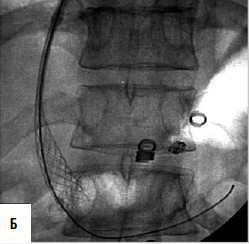

Дистальный спленоренальный анастомоз позволяет сохранить селезенку и не так резко снижает портальное давление, поскольку при этом кровь от воротной вены оттекает через сеть анастомозов и паренхиму селезенки. Такие хирургические вмешательства возможны при отсутствии симптомов печеночной недостаточности, грубых нарушений функционального состояния других органов. При функциональной ограниченности жизненно важных органов и систем целесообразно выполнить декомпрессию портальной системы с помощью чрезъяремного внутрипеченочного порто системного шунтирования (TIPS) (рис. 90). Операция осуществляется по следующей технологии: катетеризируют яремную вену, затем катетер проводят в верхнюю полую и потом в одну из печеночных вен. Далее катетер через ткань печени (перфорируя ее) проводят в одну из портальных вен. Баллонным катетером канал в печени между кавальной и портальной системами расширяют до 6–8 мм и стентируют специальным каркасомстентом.

Рис. 90. Операция чрезъяремного внутрипеченочного портосистемного шунтирования (TIPS): А – схема операции; Б – этап постановки стента; В – контроль проходимости стента